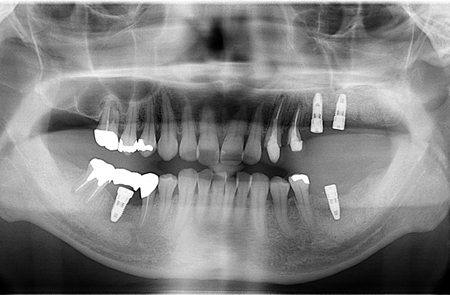

術前パノラマX線写真

術後レントゲン写真